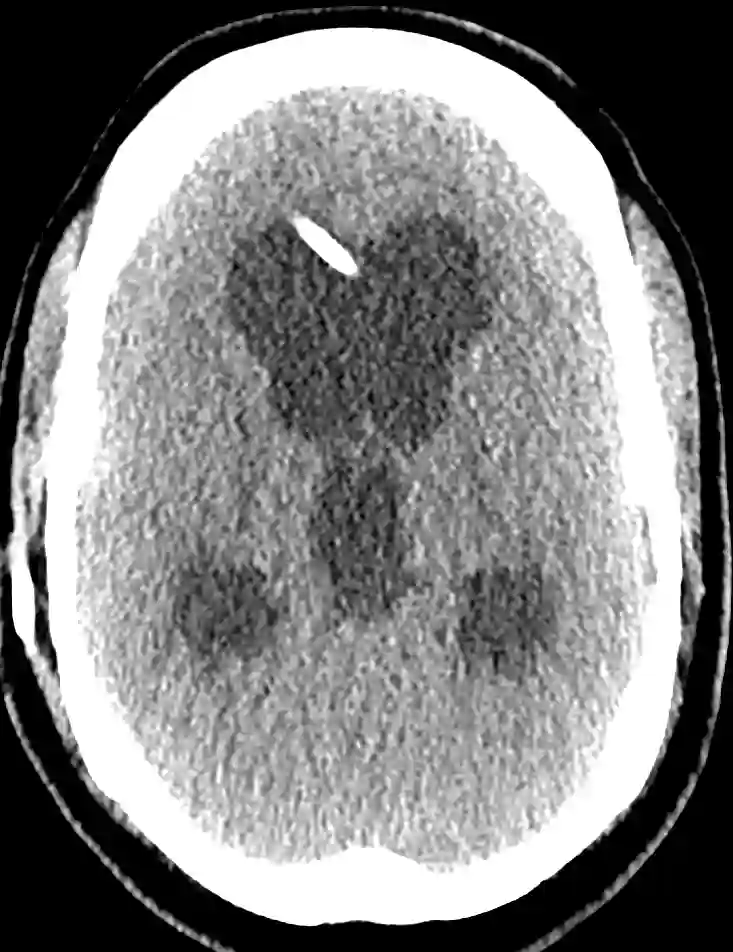

CT Shuntdysfunktion Hydrocephalus

Axiales CT Bild eines Patienten mit einem Hydrocephalus im Rahmen einer VP-Shunt Dysfunktion.